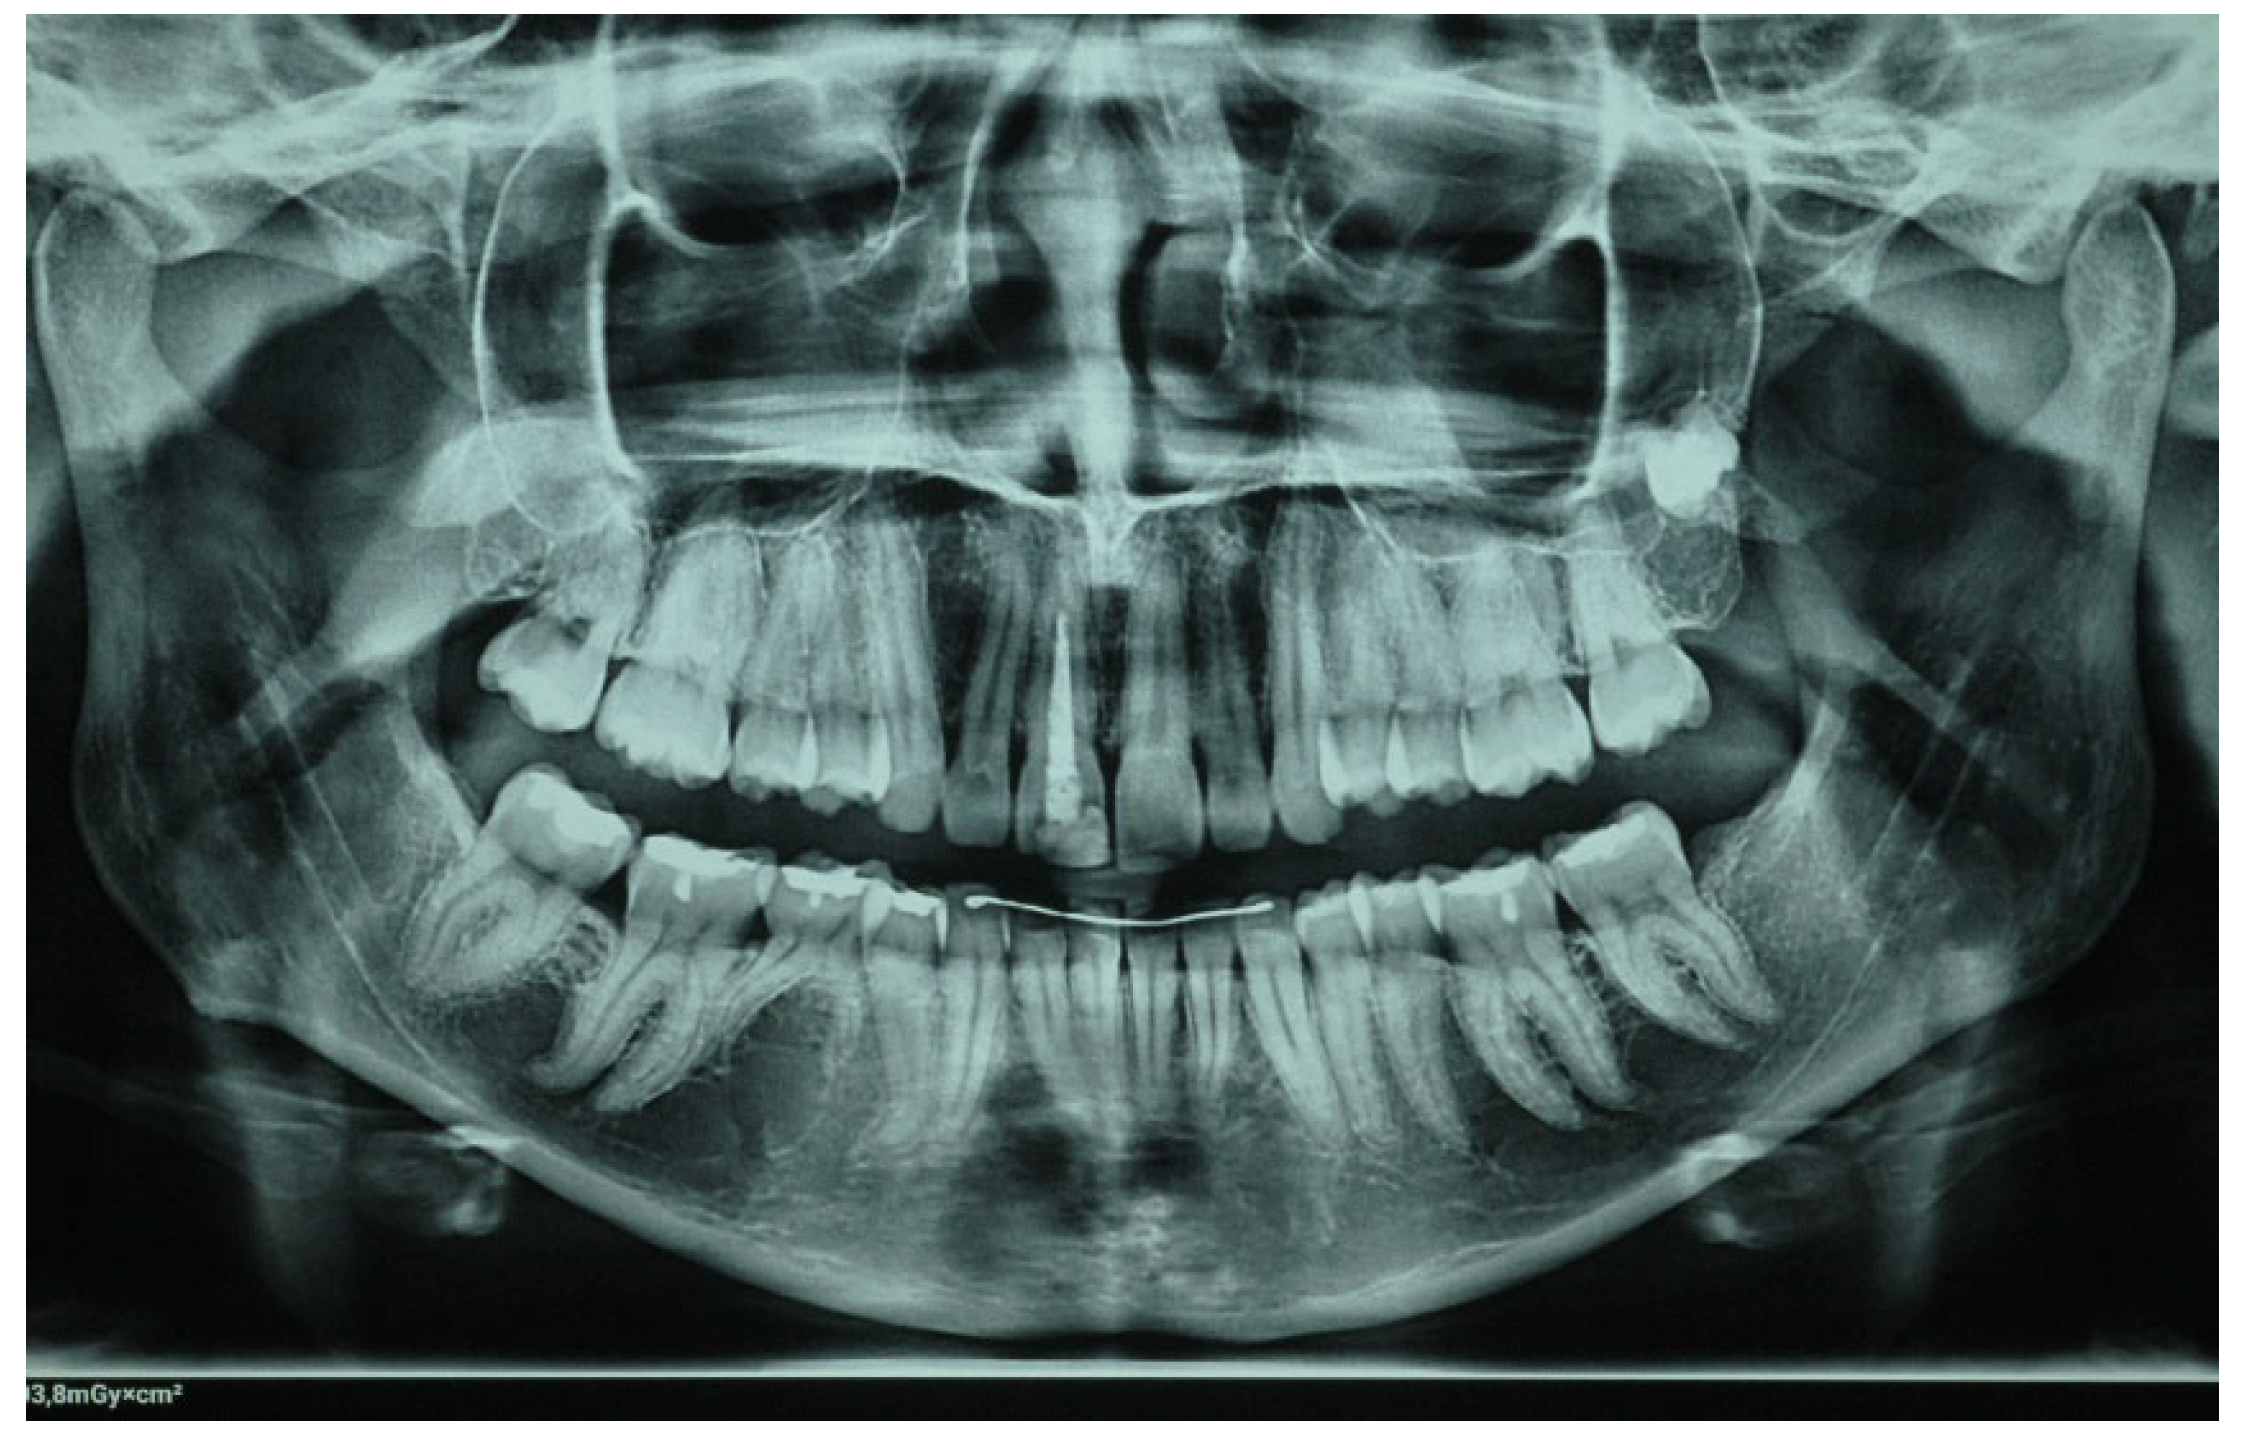

2. Clinical Case

- Porcelain veneers provide a reliable and conservative procedure for the aesthetic restoration of endodontically treated teeth that have undergone discoloration.

- For better aesthetic results, in cases of intrinsic discoloration, an internal tooth bleaching procedure may precede.

- Considering bonding and cementation, adhesively cemented high translucency monolithic zirconia seems to be a suitable option for veneers.